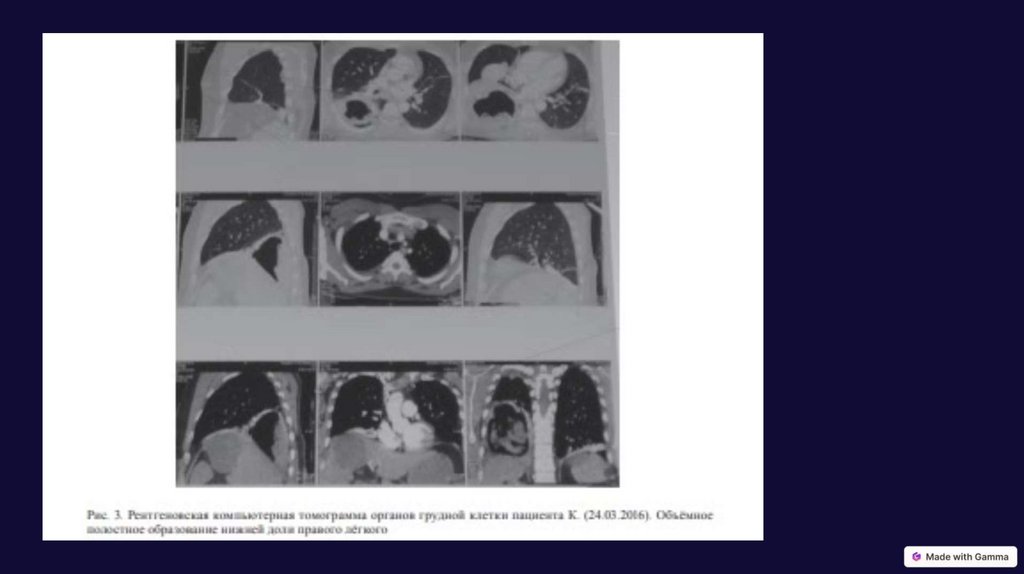

Эхинококкоз легкого

Информативность лучевой диагностики в выявлении эхинококкоза легкого составила специфичность - 98,2% ,

чувствительность - 94 %